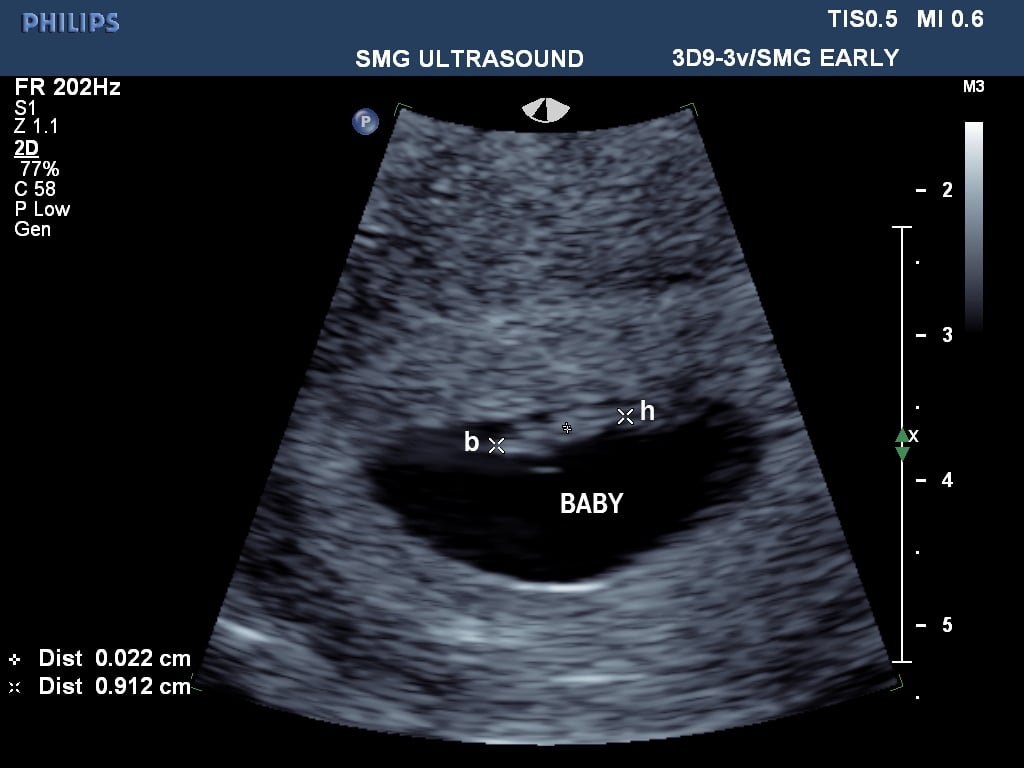

Here's our little one, measuring one day behind our due date based on LMP, but Dr. didn't see the need to adjust it and confirmed I'm 6 wks 4 days. We didn't get to hear the heartbeat, but we got to see it flutter and beat on the screen, which was so magical to me! I can't believe this is real life.

Happy to report that ultrasound looked normal, due date stayed the same, 6w+5d & Jan. 21 EDD. Going back in about a week for another ultrasound and some blood work. This is the best pic she could get (damn tilted uterus!). DH wasn't allowed back with me until the very end and we just got to see this on the screen. We saw a fluttering heartbeat but that's it. I was told it was too soon and dangerous to do a doppler

Happy to report that ultrasound looked normal, due date stayed the same, 6w+5d & Jan. 21 EDD. Going back in about a week for another ultrasound and some blood work. This is the best pic she could get (damn tilted uterus!).

DH wasn't allowed back with me until the very end and we just got to see this on the screen. We saw a fluttering heartbeat but that's it. I was told it was too soon and dangerous to do a doppler